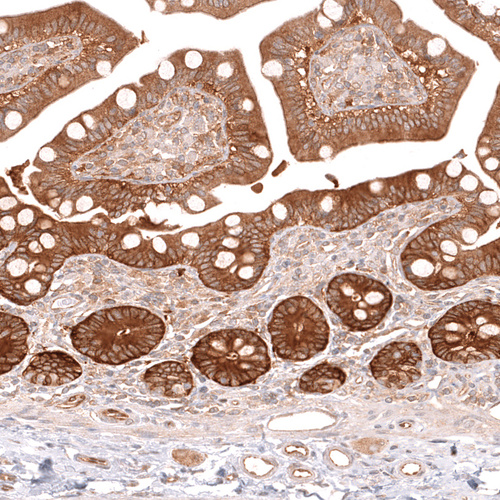

Immunohistochemical staining of human salivary gland shows strong cytoplasmic positivity in glandular cells.